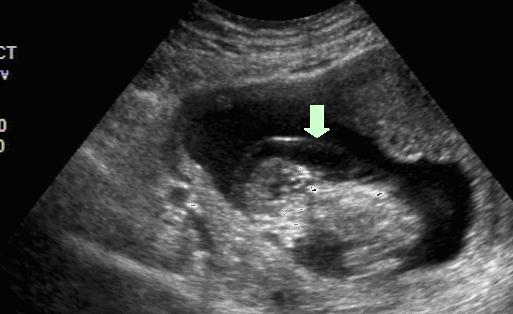

图3:NT正常的胎儿(箭头所指处即为NT) 图4:NT增厚的胎儿(箭头所指处即为NT)

唐氏综合征胎儿和正常胎儿是不同的,其颈部皮肤细胞外透明基质增加,细胞外液被大量吸附于透明基质的间隔内,使颈部皮肤发生改变,形成NT增厚。另外唐氏综合症胎儿常常合并先天性心脏病,心功能障碍时静脉回流受阻,淋巴液过多积聚在颈部,形成NT增厚。

图5:NT正常的胎儿(箭头所指处即为NT) 图6:NT增厚的胎儿(箭头所指处即为NT)